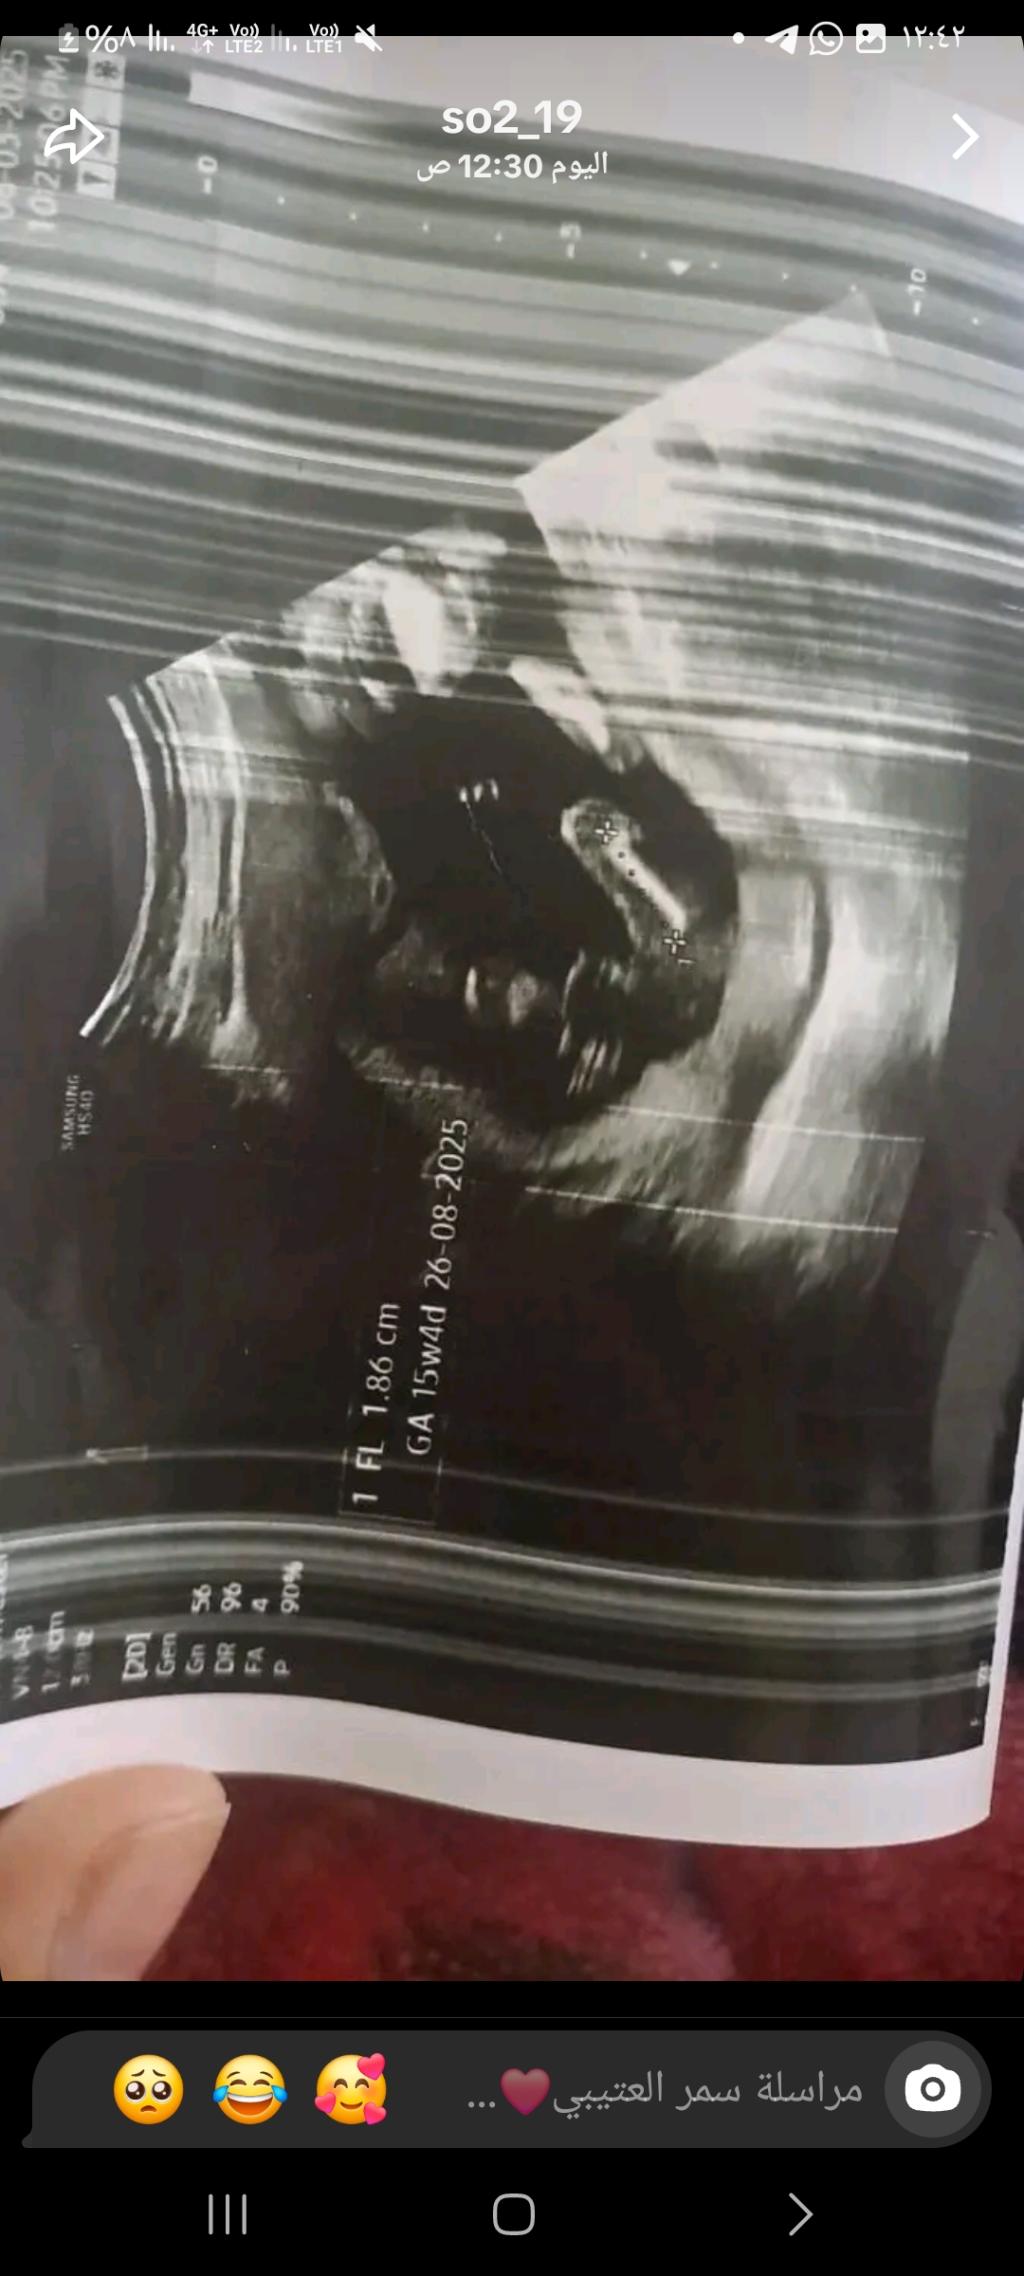

شوفو سوناري ايش النوع

الحمل والإنجاب